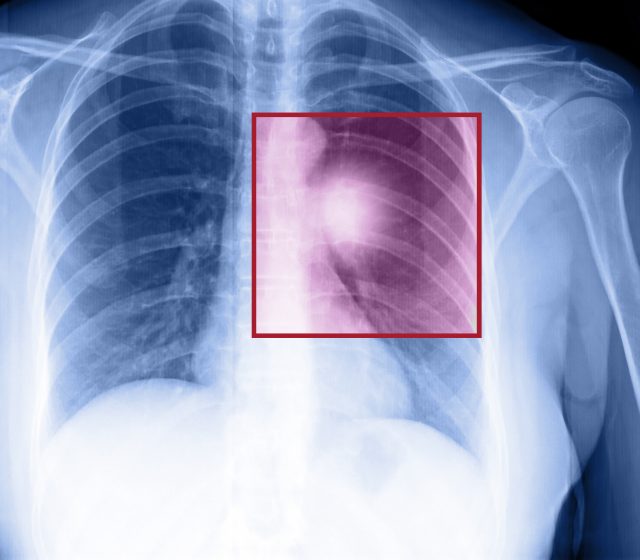

Rakovina plic

Příznaky: kašel včetně vykašlávání krve, úbytek váhy, dechová nedostatečnost, únava, bolest na prsou a další

Kolik lidí na světě jí trpí: přes 2 miliony lidí si každý rok nově vyslechne tuto diagnózu a asi 1,8 milionu na ní zemře, u nás je ročně diagnostikováno asi 7 tisíc lidí

Prevence: skoncování s kouřením (po 10 letech bez cigarety se riziko karcinomu snižuje na polovinu, screening)

Délka léčby: závisí na pokročilosti nálezu

Karcinom plic bývá druhou nejčastější příčinou smrti mužů a žen při úmrtí na nádorové onemocnění. K rozvoji onemocnění dochází v 80 až 90 % případů u kuřáků.

Rozlišuje se malobuněčný karcinom a nemalobuněčný karcinom plic, přičemž na každý z nich zabírá jiná léčba. Pokud není karcinom léčen, šíří se v podobě metastáz do dalších tkání a orgánů.

Malá šance na záchranu

Diagnóza se stanovuje na základě příznaků, potvrzuje ji rentgen hrudníku, biopsie nebo CT vyšetření. Nemalobuněčné karcinomy jsou odstraňovány chirurgicky, kdežto malobuněčné lépe reagují na chemoterapii a radioterapii.

Bohužel prognóza je u nemoci obecně špatná, navíc bývá většinou zachycena až v pokročilé fázi. U nemalobuněčného karcinomu je šance na přežití po pěti letech 70 %, u malobuněčného jen 5 %.